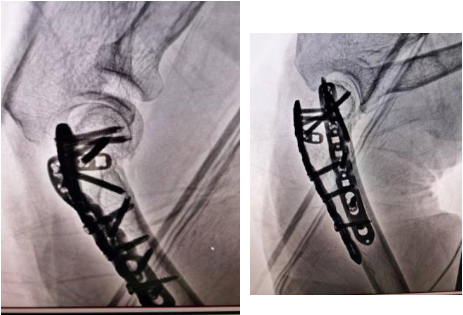

家住济南的于先生因摔伤致右髋部疼痛来院急诊就诊,X线显示右侧股骨颈骨折。经术前评估,专家组决定使用机器人辅助导航置钉进行微创手术。传统的股骨颈骨折微创手术需要手术医生在有限的视野下,凭借对解剖组织的记忆和空间构想,配合术中X光透视来完成手术操作。李连欣主任团队通过机器人导航系统,完成术中实时3D建模,在此基础上完成骨折复位,并通过智能规划进行可视化辅助置钉,手术迅速、微创,股骨颈骨折复位固定良好。